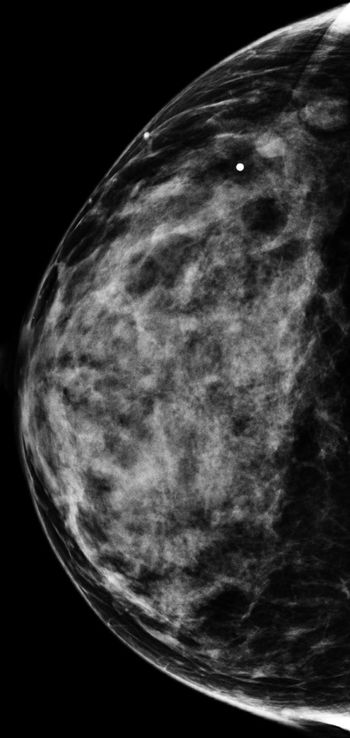

50-year-old patient presented for screening mammogram. Extremely dense breast tissue was noted.